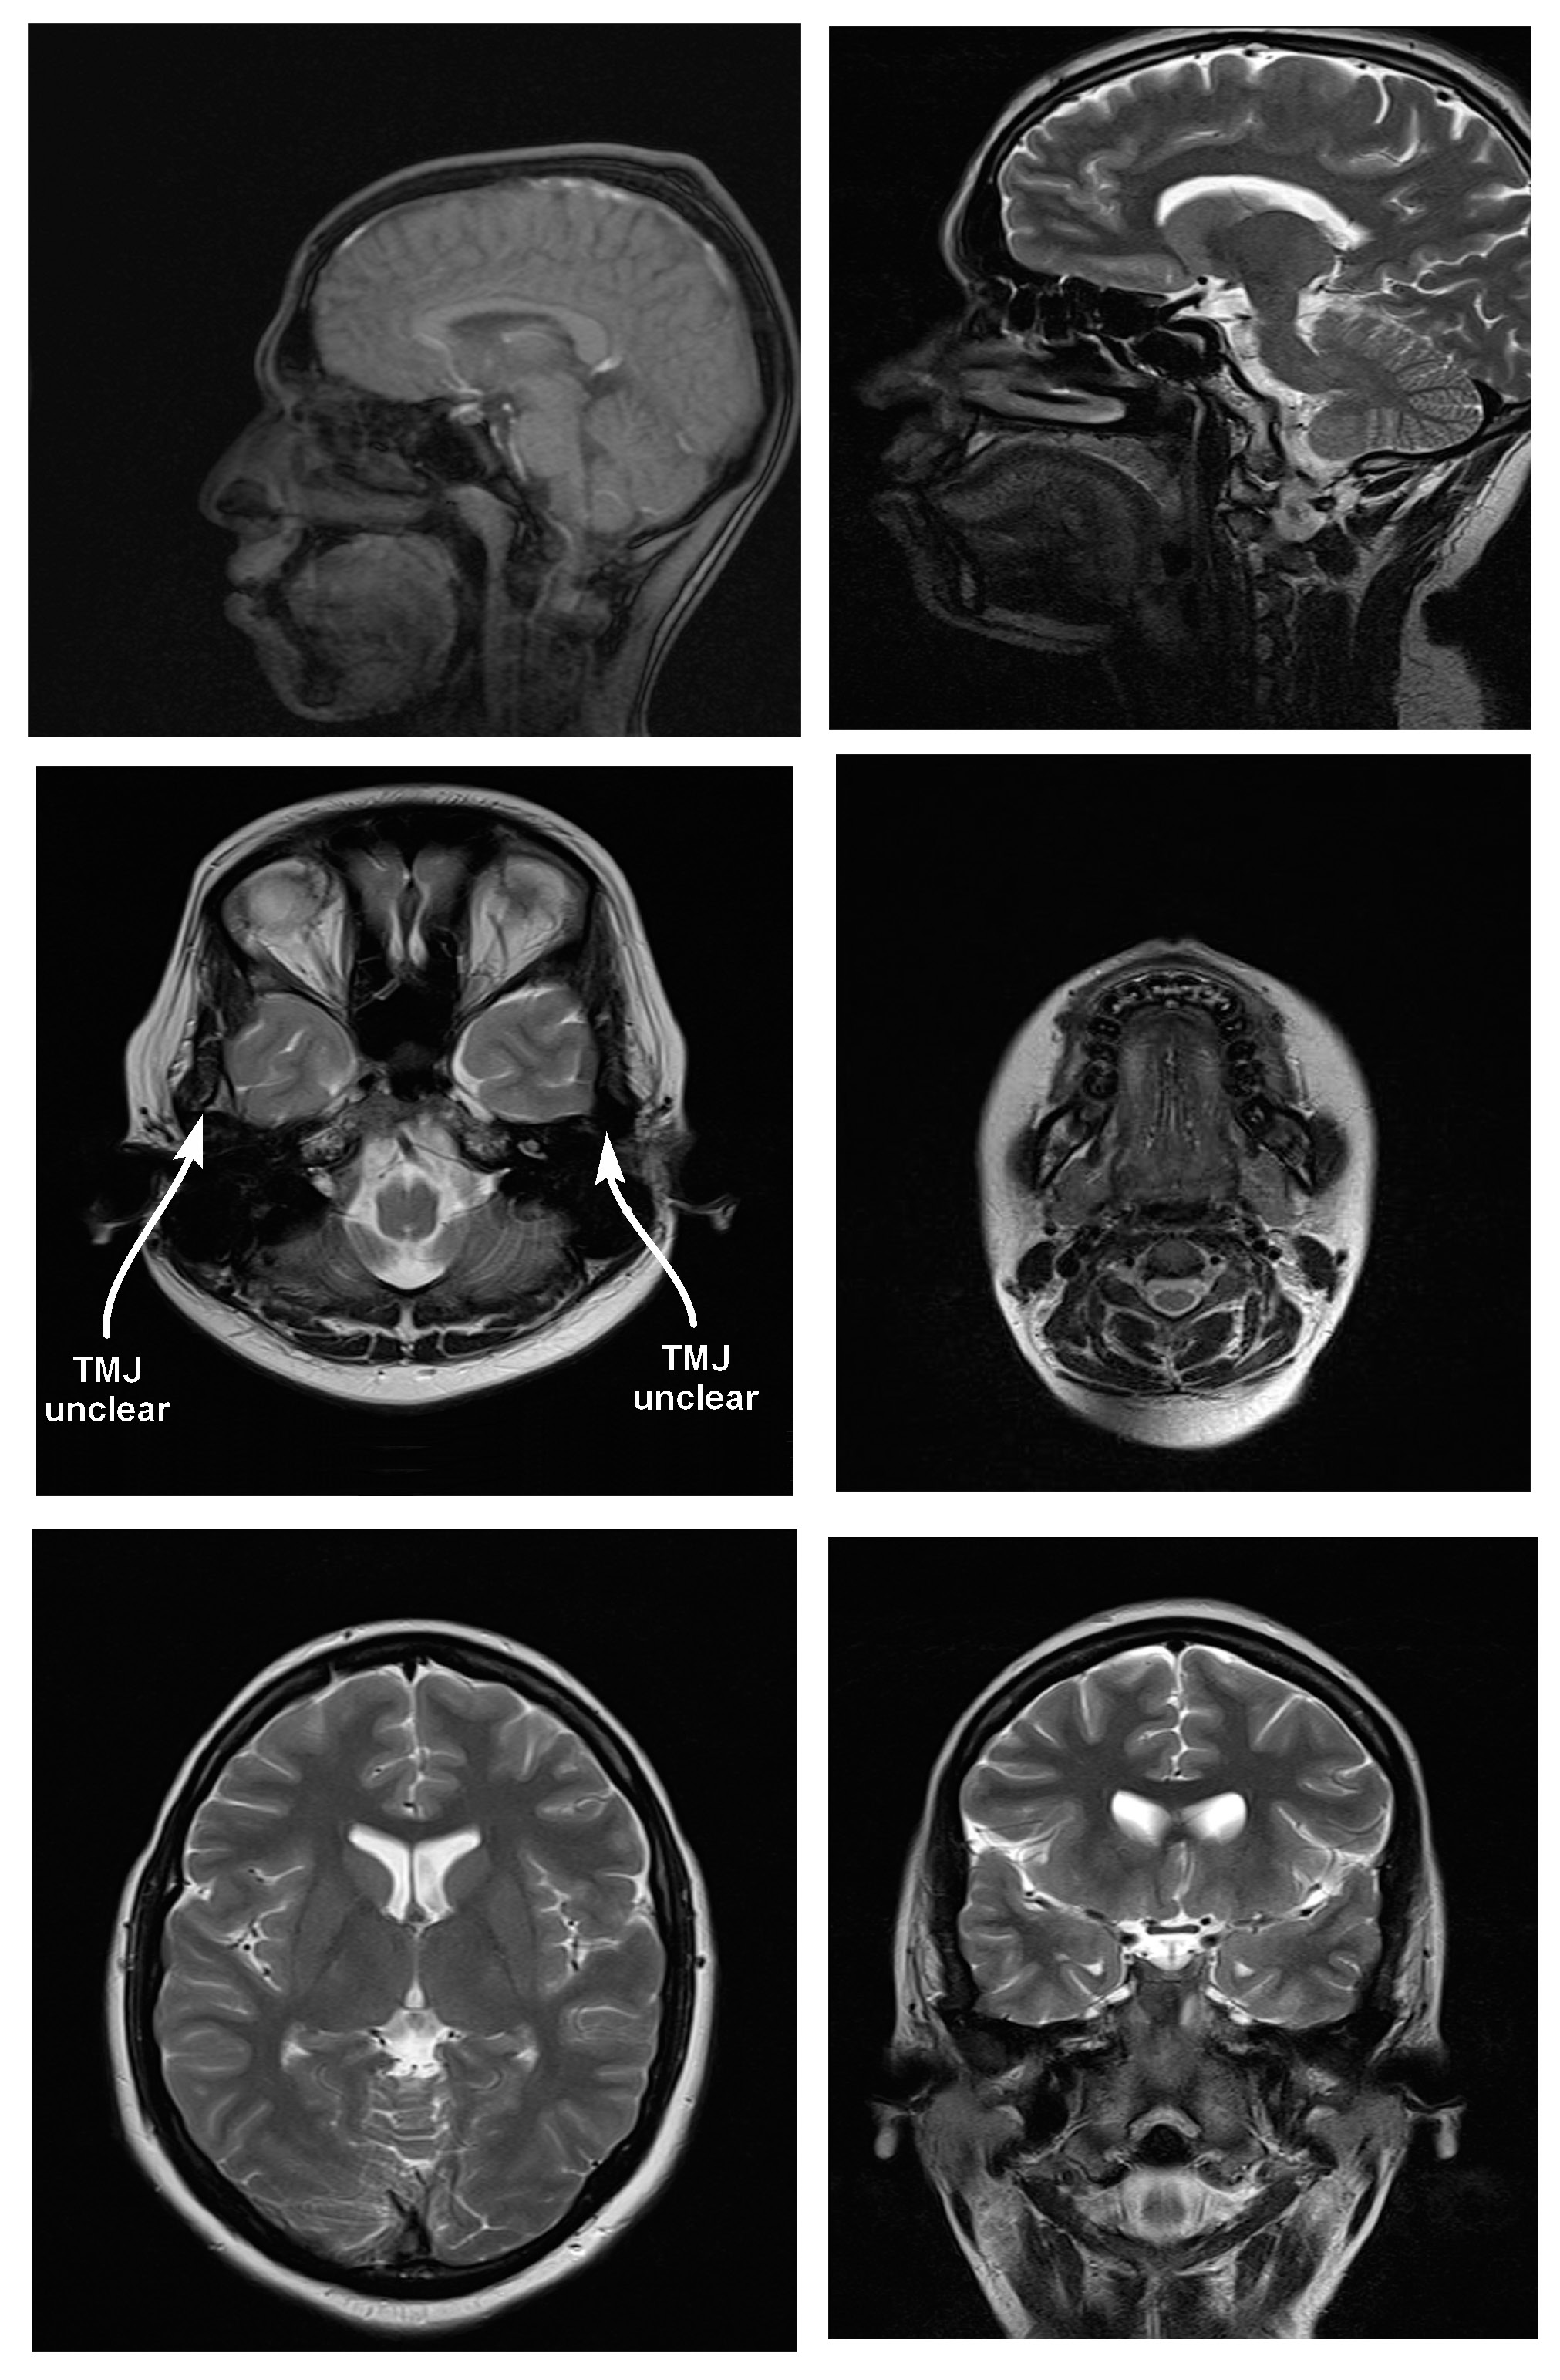

Magnetic resonance imaging scans were taken for all 38 subjects to study diagnostic image quality. Since the orthodontic appliances were securely bonded with orthodontic composite, there were no special precautions taken regarding the possible dislodgement and heating of the appliances, as previous studies had found changes in the temperature of the appliances to be clinically insignificant (within 1°C).16 The MRI scans for all types of bracket and retainer materials are shown in Figure 1, Figure 2, Figure 3, Figure 4, Figure 5, Figure 6, Figure 7, Figure 8, Figure 9, Figure 10. Non-diagnostic or unclear ROI are marked with arrows. None of the patients reported any discomfort or pain during MRI examination. The MRI scans were analyzed by a panel of 6 qualified and licensed radiologists, who assessed their diagnostic quality. The scans were compared with controls that included images from the archives of the Department of Radio-Diagnosis of Kamineni Institute of Medical Sciences. The radiologists ranked the images according to the distortion observed in the abovementioned ROI, using the modified receiver operating characteristic (ROC) analysis of distortion scoring system (Table 2), as described by Elison et al.17 In this method of distortion classification, a score of 3 represents the cut-off point for clinical usability. Images with a score of 3 have moderate distortion or artifacts, but they can still be used for diagnosis.

In the present study, stainless steel buccal/labial and lingual orthodontic brackets caused more distortion of cranial MR images and received higher distortion scores for all anatomic sites than other orthodontic bracket and retainer materials. The mean distortion score assigned by the radiologists to stainless steel appliances was 3.67. According to the anatomic landmarks, it was 4 by the same radiologists for TMJ, the tongue, the maxilla, the mandible, and the maxillary sinus, which means maximum distortion of the MR images. However, it was only 1.16 for the posterior cerebral fossa. This indicates that stainless steel buccal/labial and lingual brackets caused distortion that was most severe in the anatomic sites adjacent to them. The mean score of 1.16 for the posterior cerebral fossa means that there was almost no distortion, which shows a pattern of reduced artifacts with an increasing distance of the anatomic site from the brackets.

Since stainless steel buccal/labial and lingual brackets consistently had higher distortion scores, the MR images were considered non-diagnostic. The results of this study are similar to those obtained by Patel et al.,8 Elison et al.,17 Razdan and Rani,23 Beau et al.,24 Zhylich et al.,25 and Cassetta et al.26 However, they are contradictory to the research done by Sadowsky et al., since an older version of an MRI machine was used in their study.12